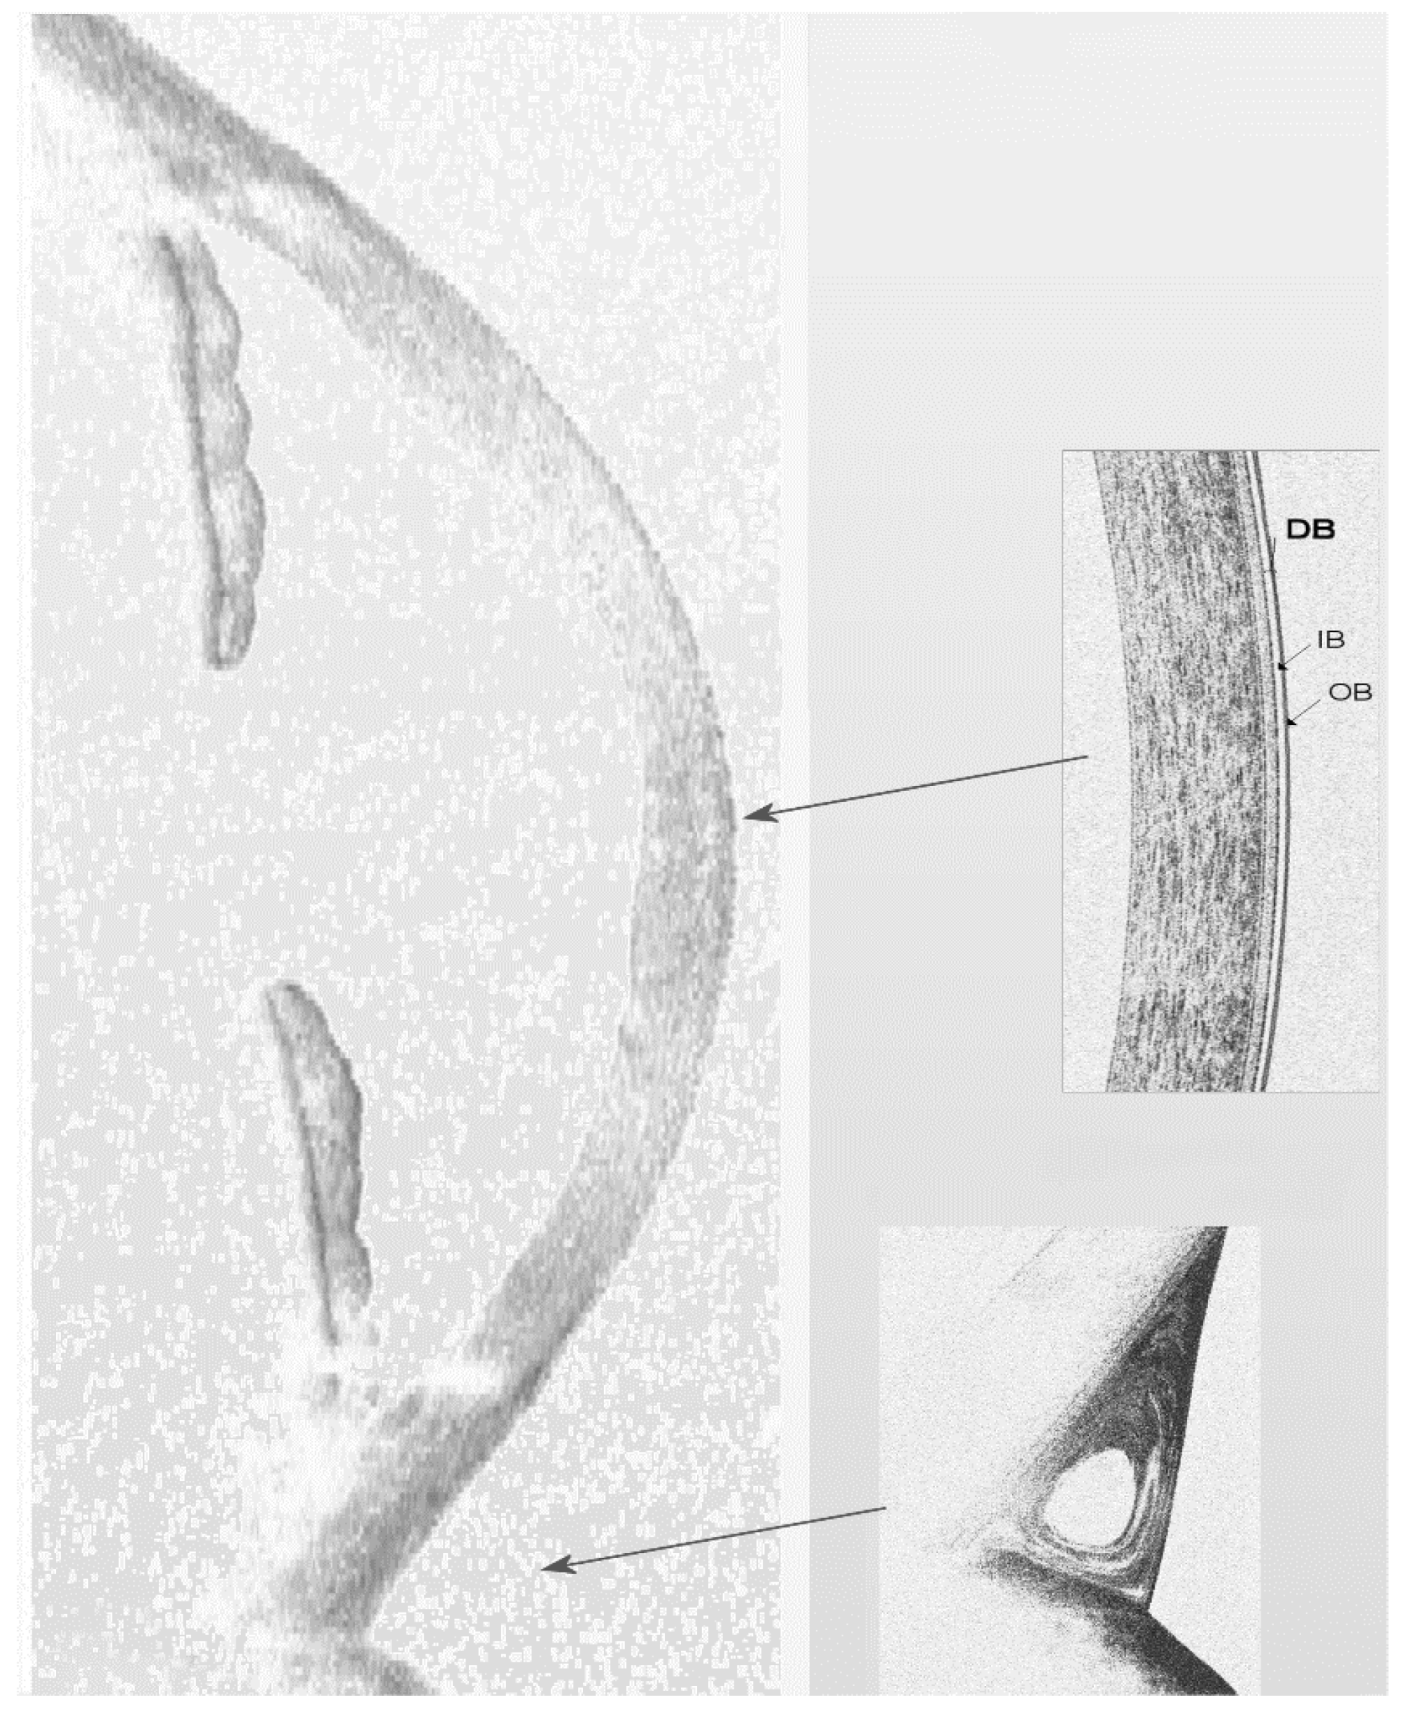

4. Structure and Appearance of the Tear Film